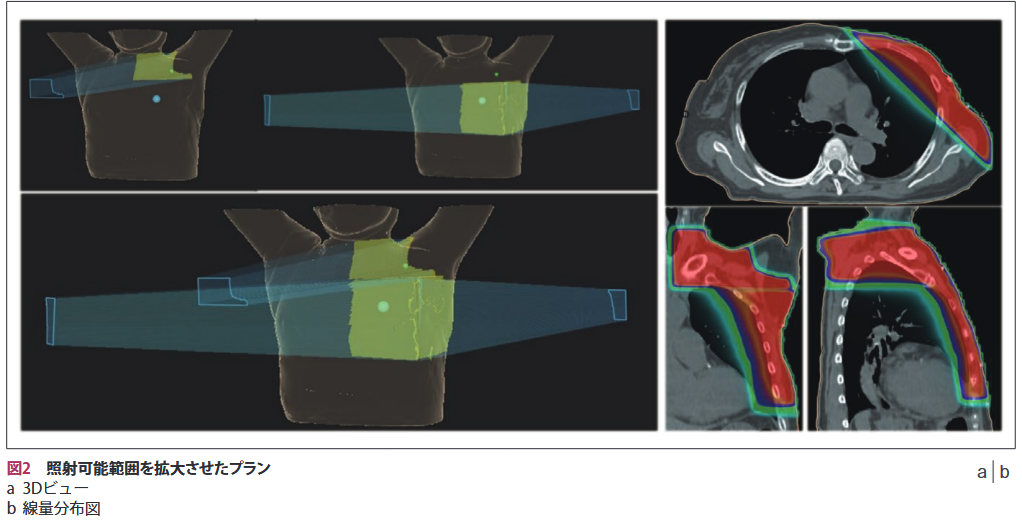

照射野はMLCのみで整形され、最大照射野サイズは20×20cmである。MLC幅は中央部40mmまでが2.5mm、その他が5mmである。MLCの高さは11cm、長さは26cm、アイソセンタ面における最高速度は65mm/sである。また、MLC位置精度は±0.5mm以内を達成している。ジンバル駆動式照射ヘッドを利用することで、照射可能範囲を30×30cmまで拡大することができる。図2に照射可能範囲を拡大させたプランの例を示す。鎖骨上側と胸壁側へジンバルを回転させ、照射野のつなぎ目はMLCで調整した。